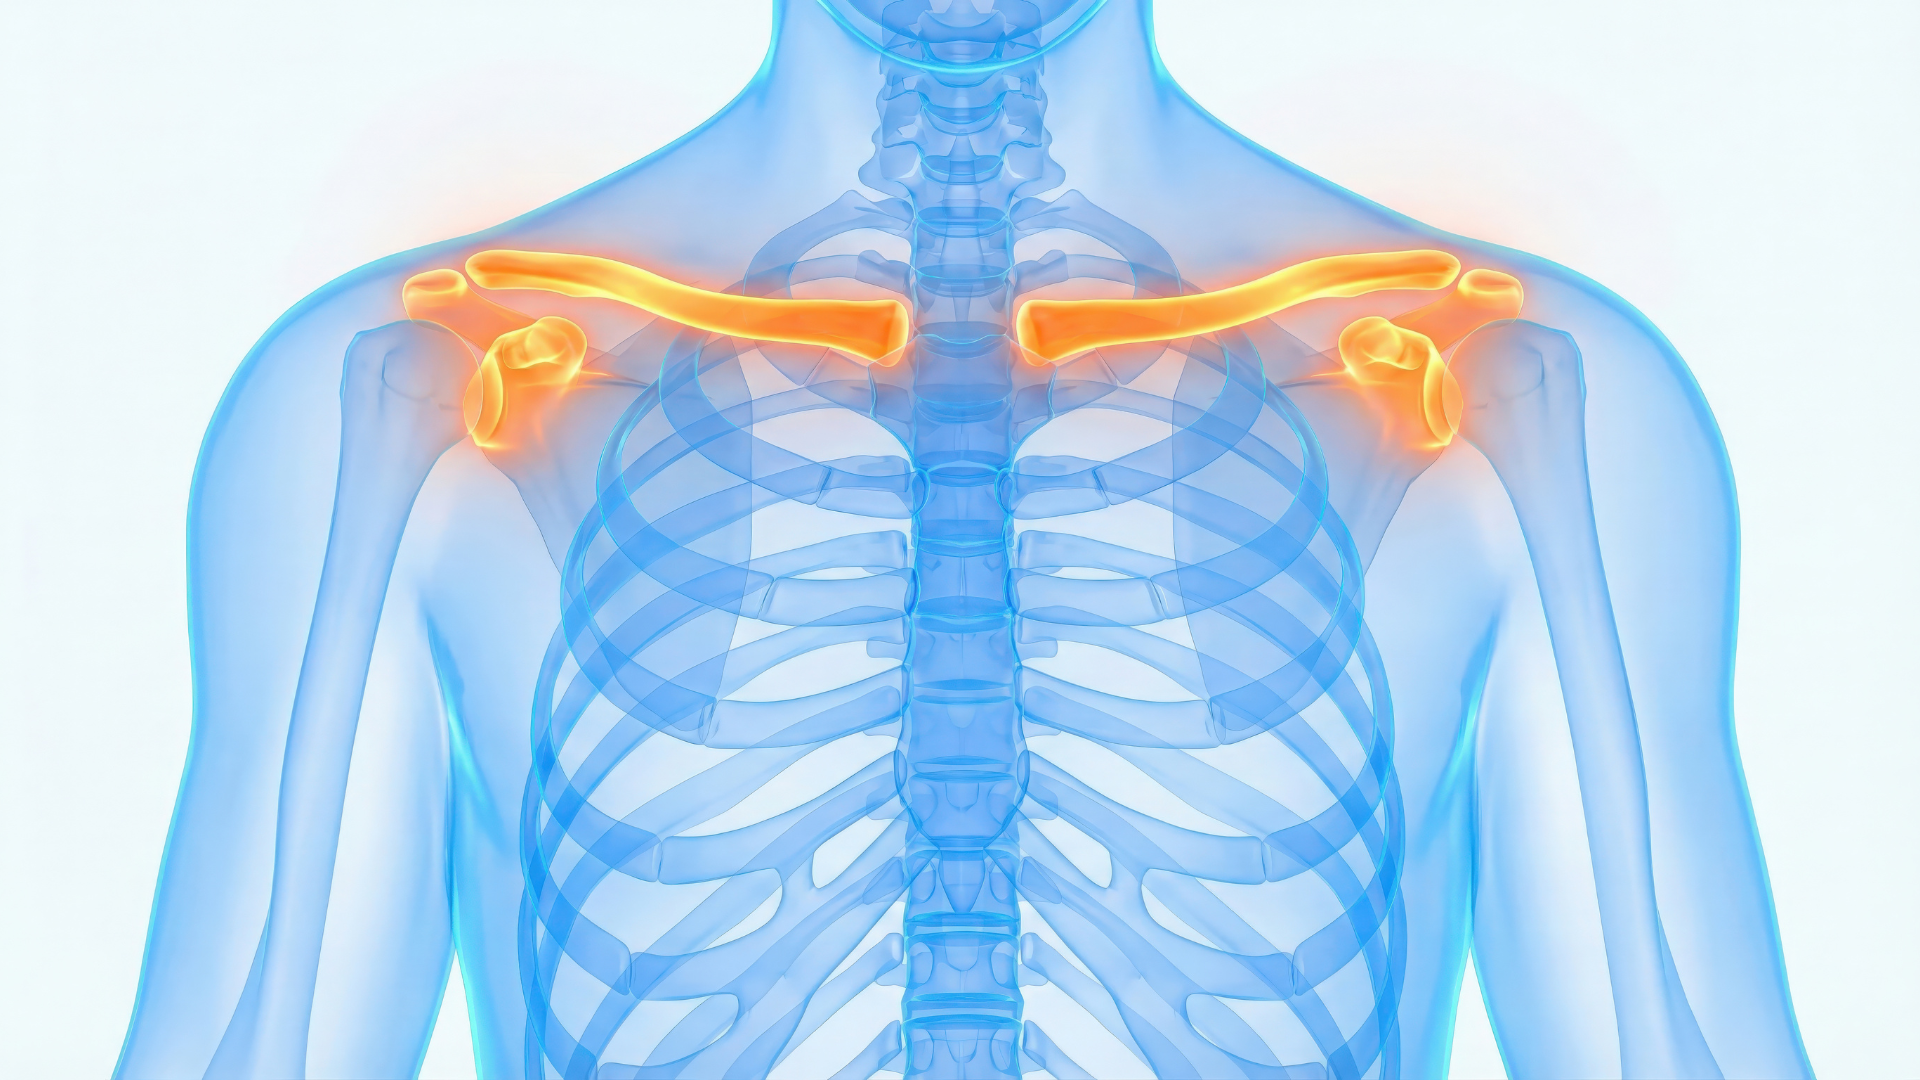

Xương đòn là xương dài nhưng mảnh mai, được xem là xương duy nhất nối trực tiếp chi trên với bộ xương trục của cơ thể. Nó đóng vai trò như một “thanh chống” vững chắc cho vùng vai, giúp duy trì khoảng cách giữa cánh tay và thân mình. Nhờ cấu trúc đặc biệt này, xương đòn hỗ trợ chi trên thực hiện các động tác rộng rãi mà không bị hạn chế bởi thân người.

Xương đòn nằm ngang phía trước ngực, ngay dưới lớp da mỏng, kéo dài từ xương ức ở giữa ngực đến mỏm cùng của xương vai ở ngoài vai. Bạn có thể dễ dàng sờ và quan sát thấy xương đòn dưới da, đặc biệt khi nâng vai hoặc xoay cánh tay. Vị trí nông này làm cho xương dễ nhận biết nhưng cũng dễ bị va chạm trực tiếp.

Về giải phẫu xương đòn, xương đòn được chia thành đầu trong (khớp với xương ức ở giữa ngực), thân xương (phần cong chính, là nơi bám của nhiều cơ quan trọng như cơ delta và cơ ngực lớn) và đầu ngoài (khớp với mỏm cùng của xương vai). Thân xương là phần dài nhất, chịu lực xoắn và nén lớn từ các hoạt động nâng đỡ cánh tay.

Xương đòn tham gia vào hai khớp chính là khớp ức - đòn ở phía trong (kết nối với xương ức, giúp ổn định trung tâm) và khớp cùng - đòn ở phía ngoài (kết nối với xương vai, hỗ trợ biên độ vận động rộng). Những khớp này có dây chằng chắc chắn, đóng vai trò quan trọng trong việc ổn định toàn bộ phức hợp khớp vai.